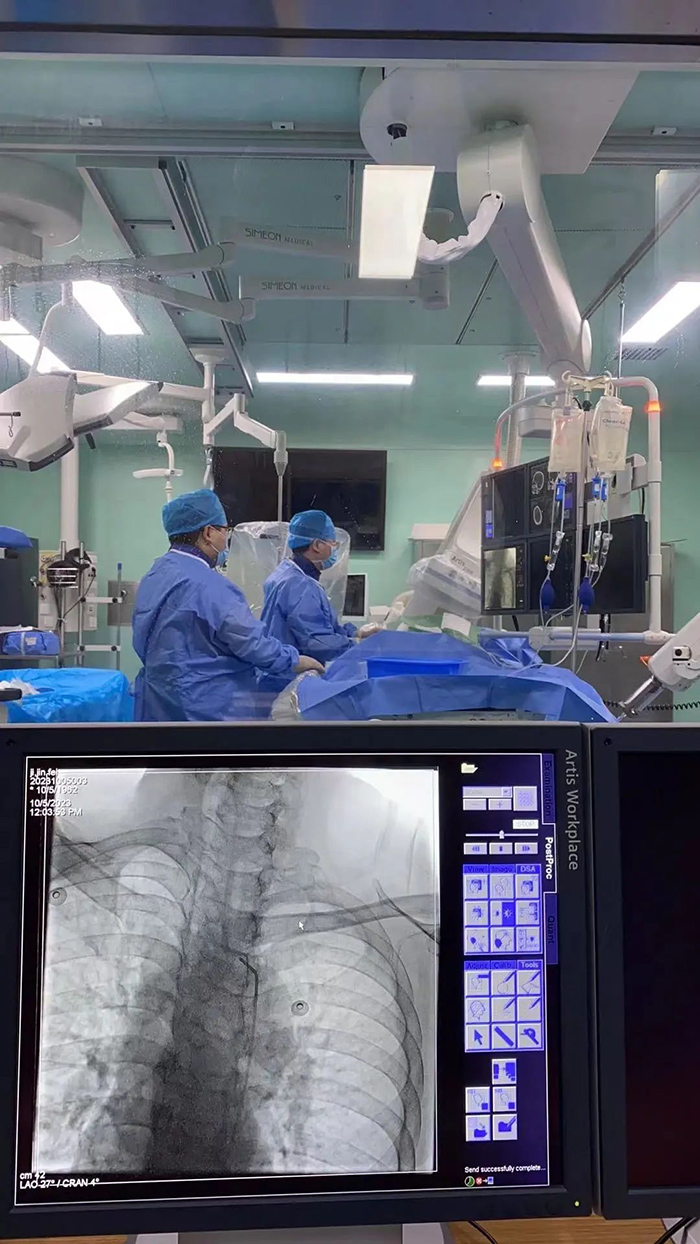

▲陈金龙主任医师、卢红腾主治医生正为患者做手术

作为配合多年的老搭档,神经内科介入团队陈金龙主任医师、卢红腾主治医师与鲁红梅护士精细操作、密切协作,有条不紊地实施左侧颈内动脉窦部次全闭塞再通术(球囊扩张、支架置入)及左侧大脑中动脉取栓术。

手术台下,林宝荣主任医师与苏宗权主治医师两位值班医生一直严密观察患者病情变化。